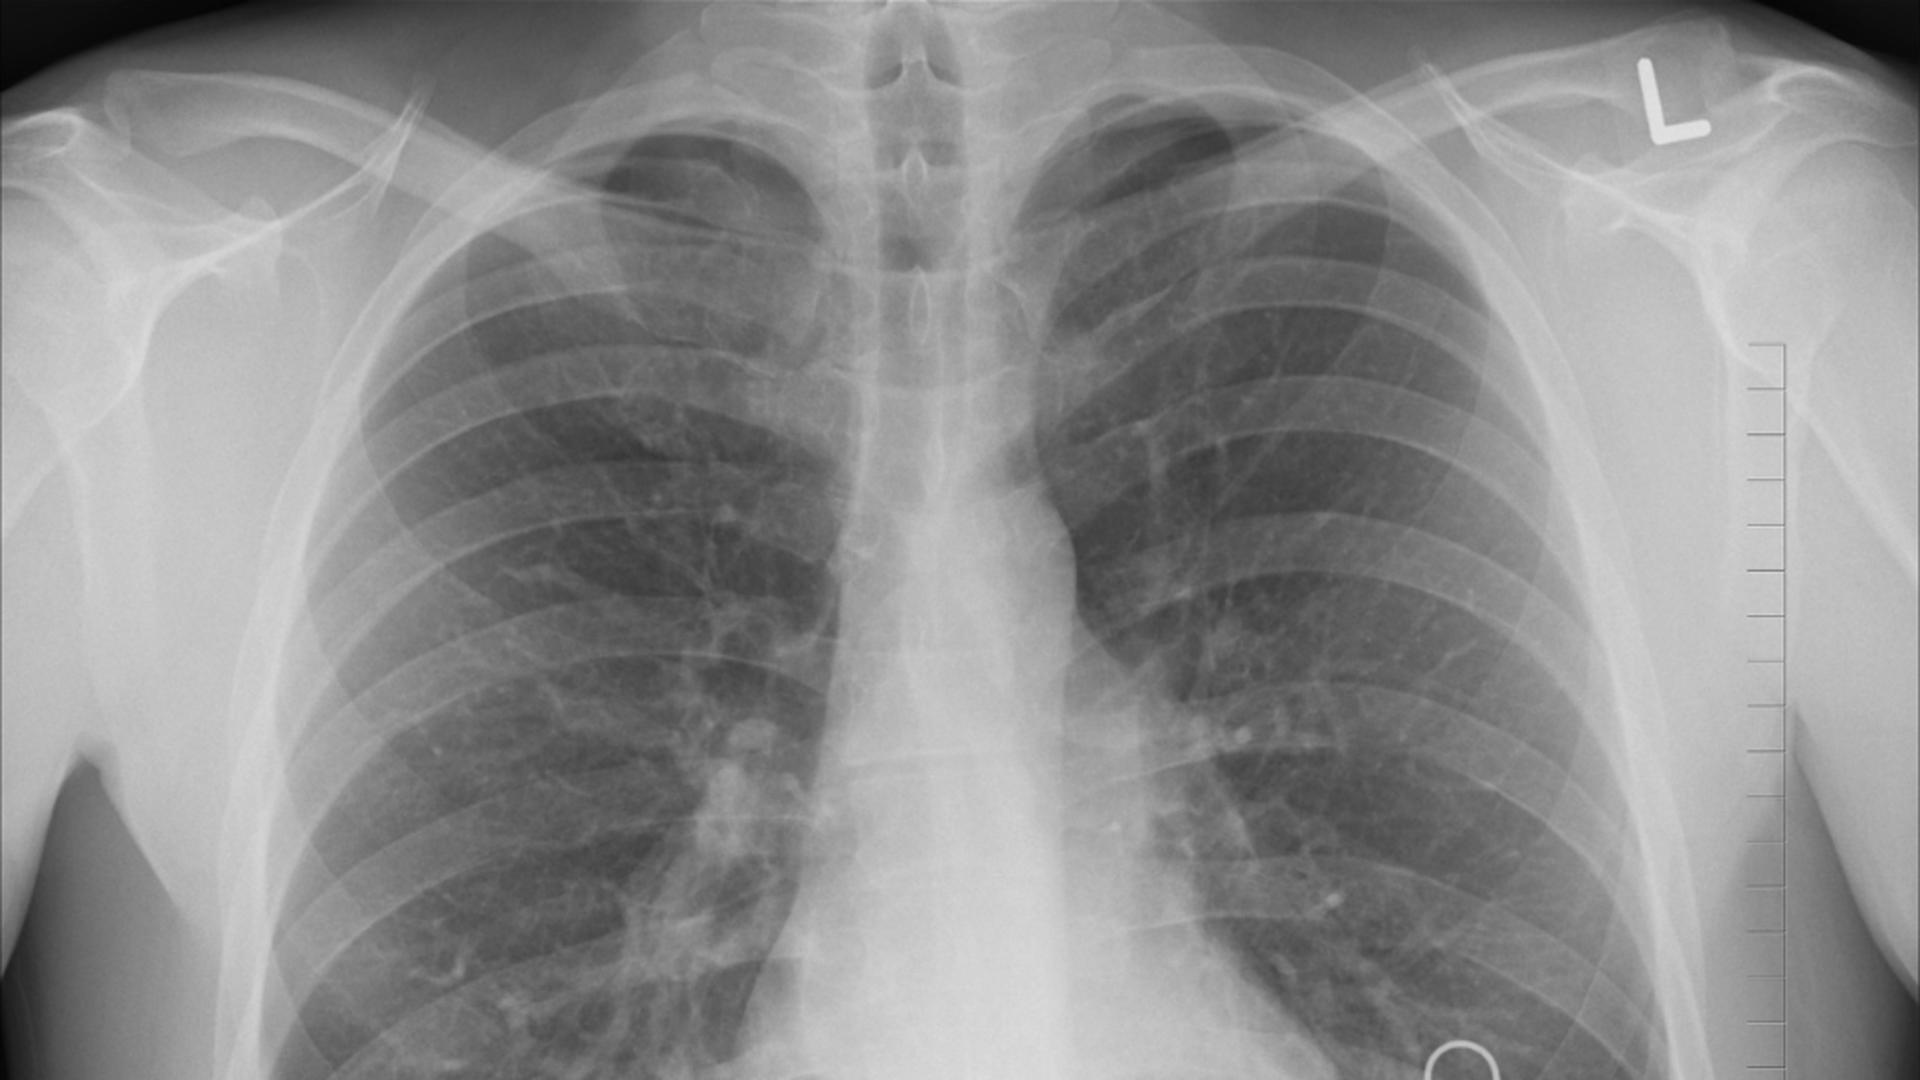

Forma gravă a bolii, legioneloza, provoacă pneumonie severă, febră mare, frisoane, tuse persistentă și dificultăți de respirație.